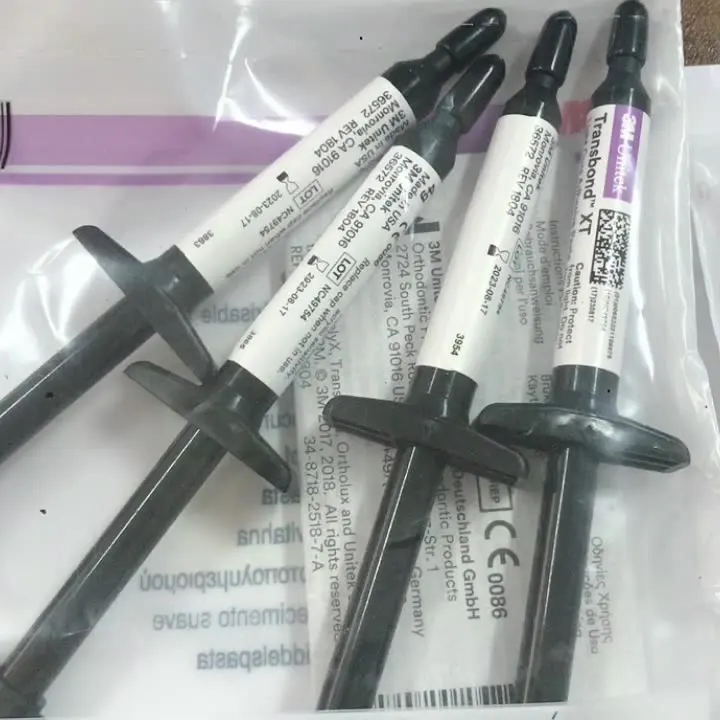

Светильник cure зубной ортодонтический 3 M XT transbond / 3 M unitek, композитная смола для ортодонтического использования, праймер